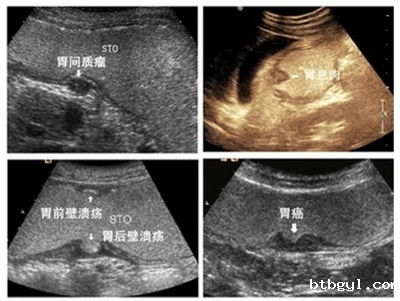

器质性病变:胃炎、胃溃疡、胃癌、胃息肉、胃囊肿、间质瘤等。

先天性病变:胃憩室、肥厚型幽门狭窄、异位胰腺、十二指肠闭锁。

功能性异常:胃动力不足、胃食管反流、胃下垂、十二指肠瘀滞等。

其它:胃结石、胃内异物及胃底静脉曲张、食管裂孔疝等。